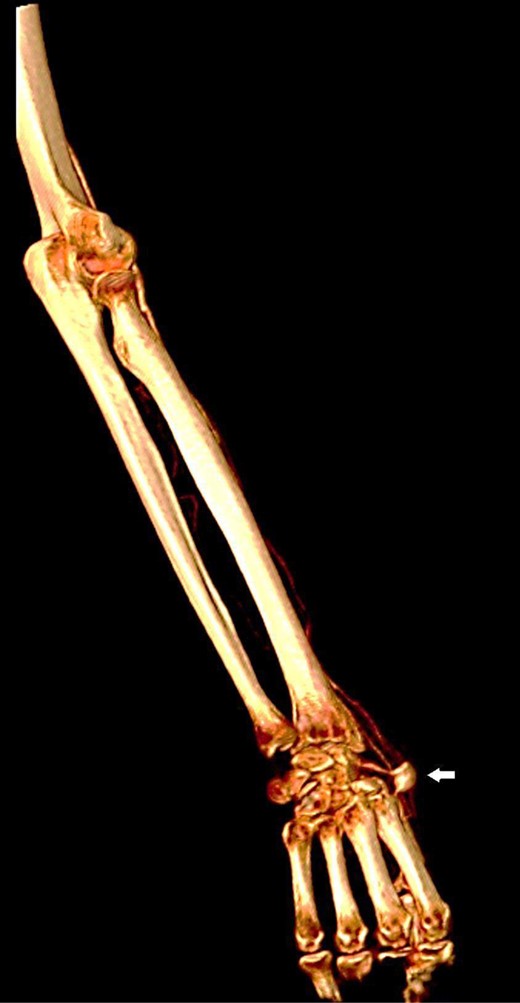

Upon physical examination, a mass of 2-by-3 cm found at the anatomical snuffbox area of the right hand, with no visible scars (Fig. 1). The mass was pulsatile, and no bruit was detected. The examination of the other arteries was negative. Later, CT angiography detected a local dilation at the distal part of the right radial artery (Figs 2 and 3). Complete body scan showed another aneurysm at the right common iliac artery measured 3-by-2.8 cm for which the patient was referred to a higher centre for possible endo-vascular intervention as it is not available in our hospital.

Reconstructed three-dimensional image shows radial artery saccular aneurysm (arrow).